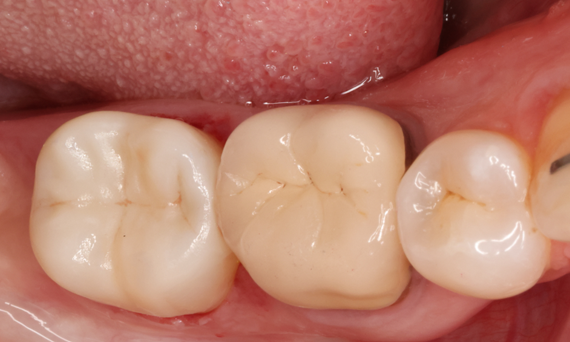

Second lower right molar in 90 minutes

A CEREC Tessera onlay

A 20-year-old female patient had endodontic treatment of her lower right 2nd molar. A chairside onlay was fabricated from the new high-strength ceramic CEREC Tessera ALD.

Before: Pre-operative clinical scenario after endodontic therapy.

After: 1 month after the CEREC Tessera onlay was bonded.

Dr. Aniruddha Nene

Pune, India